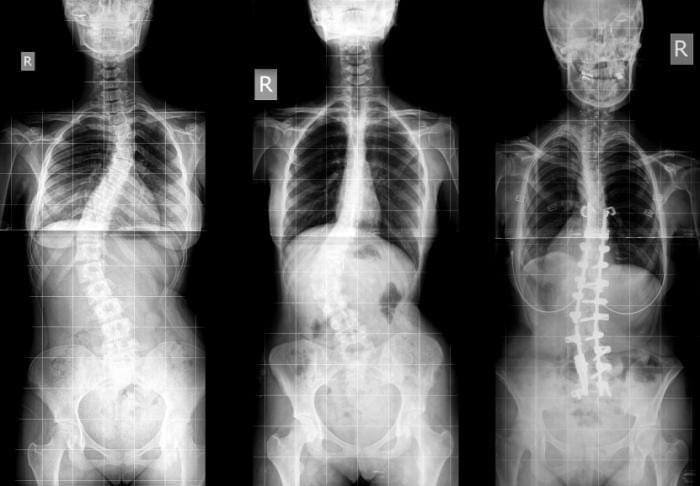

Studji dwar l-Immaġini

L-immaġini f'mard deġenerattiv tad-diska tintuża prinċipalment biex tiddeskrivi relazzjonijiet anatomiċi u karatteristiċi morfoloġiċi tad-diski affettwati, li għandha valur terapewtiku kbir fit-teħid ta 'deċiżjonijiet futuri għal għażliet ta' trattament. Kwalunkwe metodu ta 'immaġini, bħal radjografija sempliċi, CT, jew MRI, jista' jipprovdi informazzjoni utli. Madankollu, kawża sottostanti tista 'tinstab biss fi 15% tal-pazjenti billi l-ebda bidliet radjoloġiċi ċari ma huma viżibbli f'mard deġenerattiv tad-diska fin-nuqqas ta' ħernja tad-diska u defiċit newroloġiku. Barra minn hekk, m'hemm l-ebda korrelazzjoni bejn il-bidliet anatomiċi li dehru fuq l-immaġini u s-severità tas-sintomi, għalkemm hemm korrelazzjonijiet bejn in-numru ta 'osteofiti u s-severità ta' uġigħ fid-dahar. Bidliet deġenerattivi fir-radjografija jistgħu jidhru wkoll f'nies bla sintomi li jwasslu għal diffikultà biex jikkonformaw ir-rilevanza klinika u meta tibda l-kura. ("Marda tad-Diska Deġenerattiva" Fiżjopedja)

Ir-Radjografija

Din ir-radjografija ċervikali sempliċi rħisa u disponibbli b'mod wiesa 'tista' tagħti informazzjoni importanti dwar id-deformitajiet, l-allinjament, u bidliet deġenerattivi taż-żaqq. Sabiex tiġi ddeterminata l-preżenza ta 'instabilità ta' l-ispina u bilanċ sagittali, għandhom isiru studji ta 'flessjoni dinamika jew estensjoni.